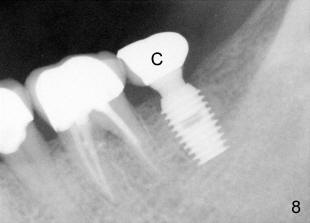

Fifty-four year old lady had had discomfort with a cantilever bridge (FPD) that restored #18 (Fig.1) and agreed to have FPD removed (Fig.2) and place implant (Fig.3: 5x8) 22 months ago. The lingual plateau of the implant was exposed due to plate perforation (Fig.4: <). At implant placement, #19 was found to have recurrent apical periodontitis. This tooth had root canal retreatment (Fig.5: 19), build-up (Fig.6: B) and crown (Fig.7: C).

A 4x6.5 non-shouldered abutment was inserted, prep and impressed for PFM on uncover. Fig. 8 PA was taken after intraoral cementation of crown (C).